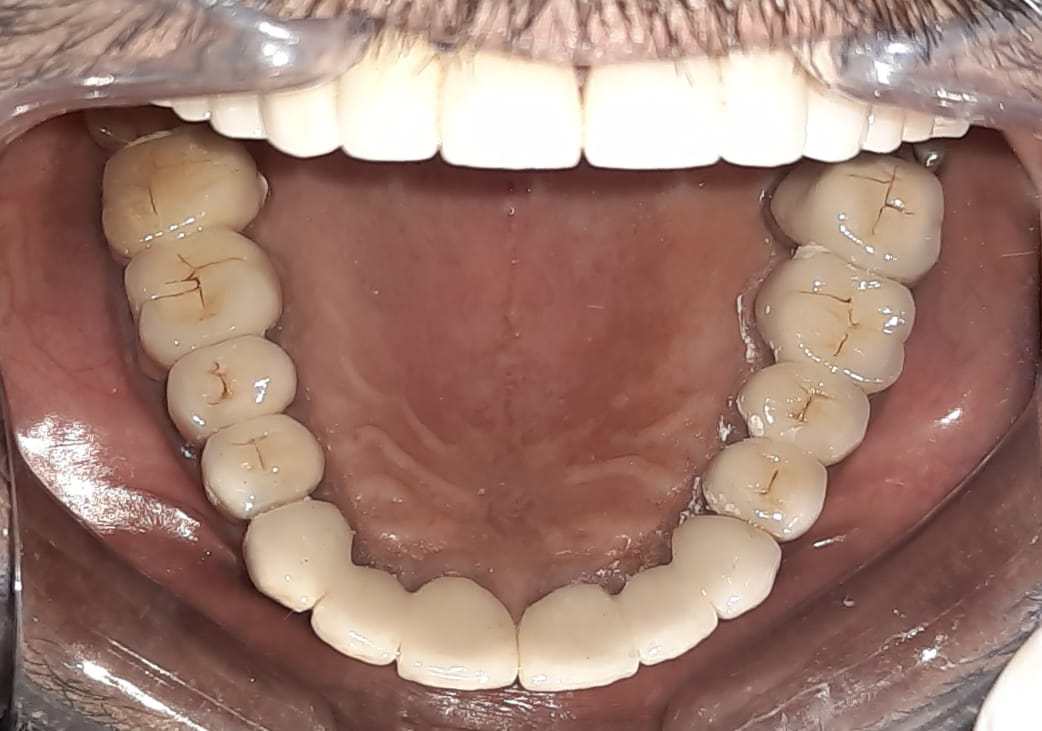

Case Scenario 1 - Full Mouth Rehabitilation

Patient wanted to get a new set of new teeth as old teeth were severely attrited and he was not able to chew. Medical history was taken and patient was fit for all the dental procedure. A detailed radiographic examination was conducted with the help of opg Treatment planning. A detailed case history along with radiological investigation and recording of of Bite of patient it was done in first visit. An appliance to relieve occlusion was given for 21 days Root canal treatment it was perform for all the teeth in subsequent visits. Occlusion was recorded using a specialised semi adjustable articulator. A temporary prosthesis was given to be used for or 15 days. A permanent Restoration was fabricated using pfm Crowns. A patience on patient end is a much needed thing as it involves time duration of of 1 to 2 months. Patient has to be absolutely serious about the treatment protocols which we are following as it involves use of appliances on patients end. Patient has to leave habit of eating Supari and tobacco as it was the cause in in severe reservation and attrition of teeth the artificial prosthesis is a finely crafted instrument that needs to be used with precision. so patients willingness and a positive mindset is Paramount in treating such cases.